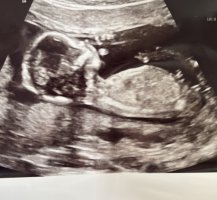

Tipper det her er en liten guttHei! Var på privat ultralyd uke 14+ 3, men jordmor turte ikke å konkludere med kjønn enda. Skal sies at hun først var veldig sikker på gutt, men ble mer og mer usikker etterhvert som hun så, og derfor ikke turte å konkludere. Er ingen ekspert på Nub-teorien, men syns jeg ser tydelig gutt på disse bildene? Blir bare veldig usikker når jordmor mente det fortsatt kan være jente, og en hoven klitoris. Hva tenker dere? hilsen alt for nysgjerrig mamma![]()

Noen som har lyst å gjette her? 13+2 føler selv jeg ikke ser noe nub, men ifølge både early glimpse og nub theory er det 85% sjans for jente

Ingen synlig nub dessverre :-/Har noen lyst til å gjette her, hvis det er noe å se på bildene i det hele tatt daEr 14+0